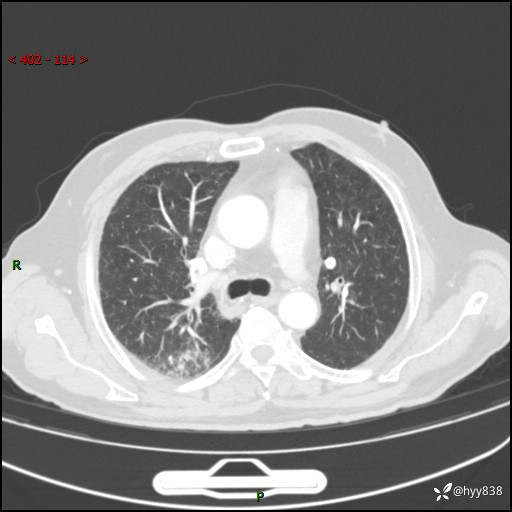

现病史:患者4月前无明显诱因后背正中间疼痛,间断阵痛,无低热、咳嗽,盗汗、咯血、胸痛、喘气等不适,2024-2-25当地市第二人民医院胸部CT提示“1.双肺感染病变;2.右肺中叶结节灶;3.双肺肺气肿并肺大泡4.主动脉及冠脉硬化,今为求明显结节性质遂来我院门诊就诊,门诊以“肺占位”收治入院。 起病以来,患者精神饮食睡眠一般,大小便正常,体力体重无明细变化。

胸部CT平扫(2024.2)